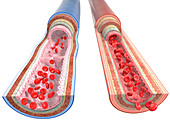

13435209 - Artery and vein, illustration

13435208 - Artery and vein, illustration

13435191 - Artery, illustration